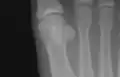

Sesamoid bones at the distal end of the first metatarsal.